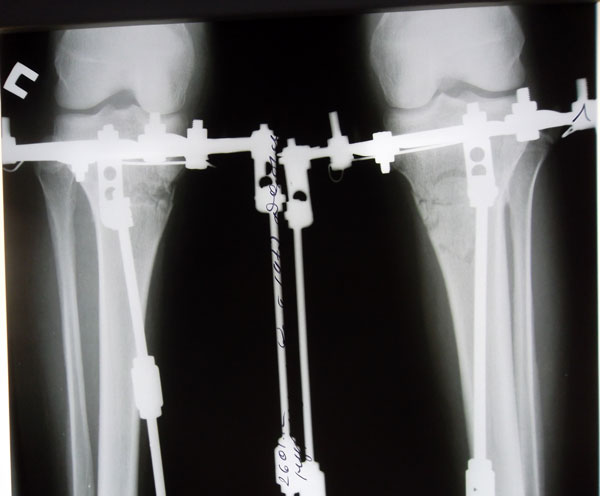

Новогодний заезд "кривоножек"!

Gauhar, как переносишь аппаратный период?

Когда снимаешь аппараты?

После снятия аппаратов движение в суставах в полном объёме. Сегодня больничный лист закрыт, выхожу на работу.